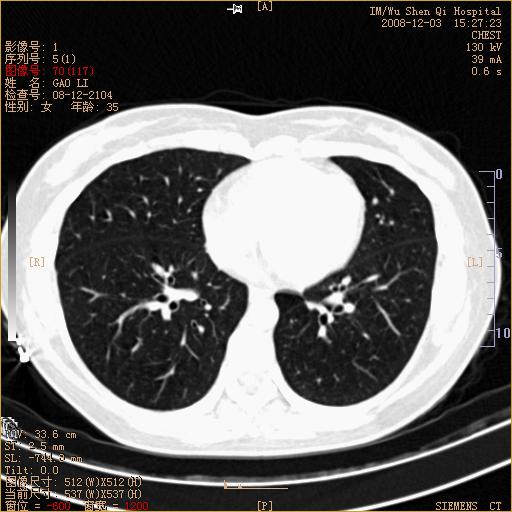

标题: CT16895:女,35岁,反复咳嗽数月,只传部分图像,是否考虑 [打印本页]

标题: CT16895:女,35岁,反复咳嗽数月,只传部分图像,是否考虑

左下肺支扩

典型“印戒征”。

印戒征,支持支扩.

左下肺扩支

印戒征,支扩